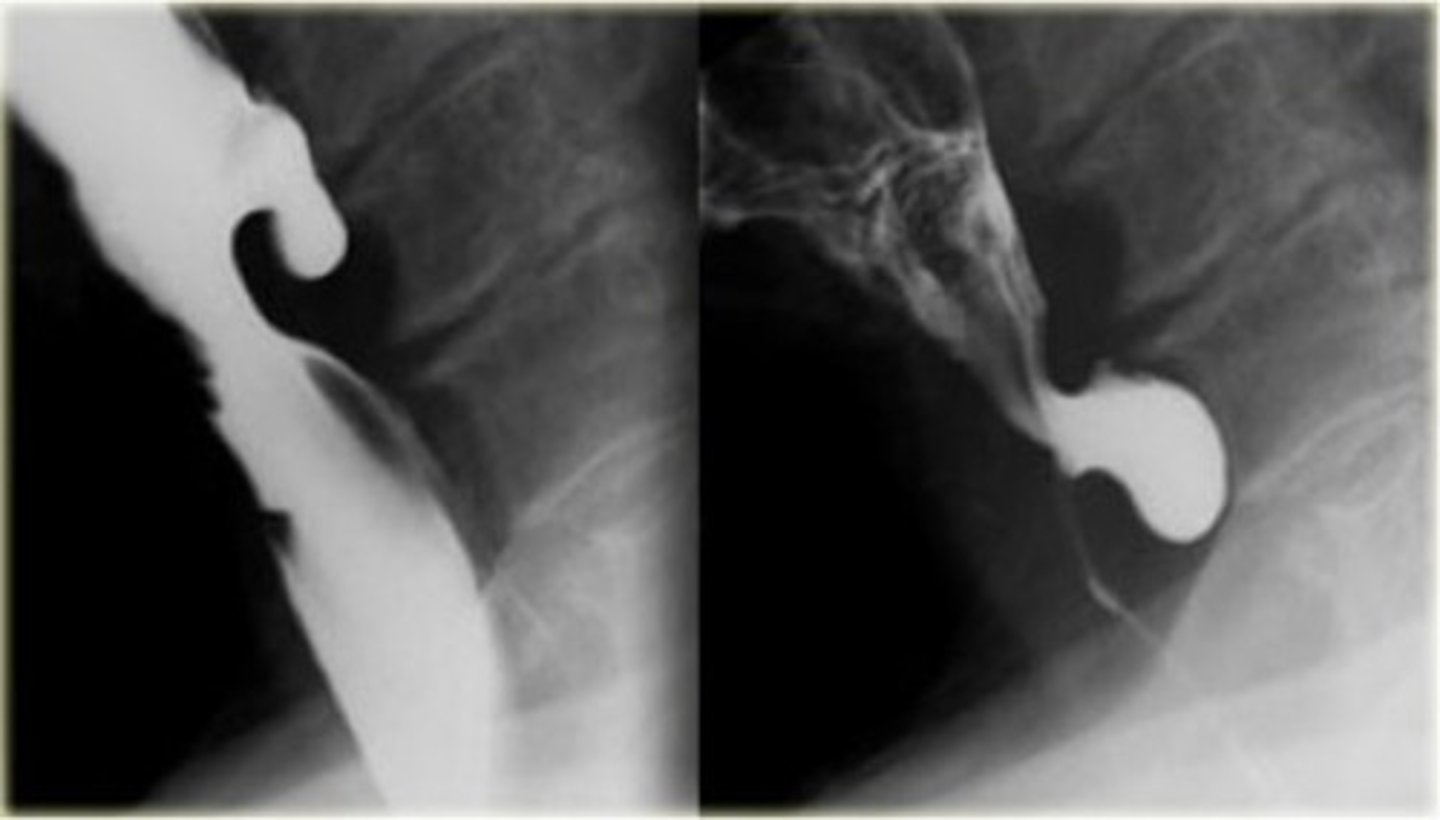

Zenkers diverticulum (pic 2)

Zenkers diverticulum (pic 3)

A: zenkers diverticulum

B: traction diverticulum (often seen in TB patients)

C: epiphrenic diverticulum